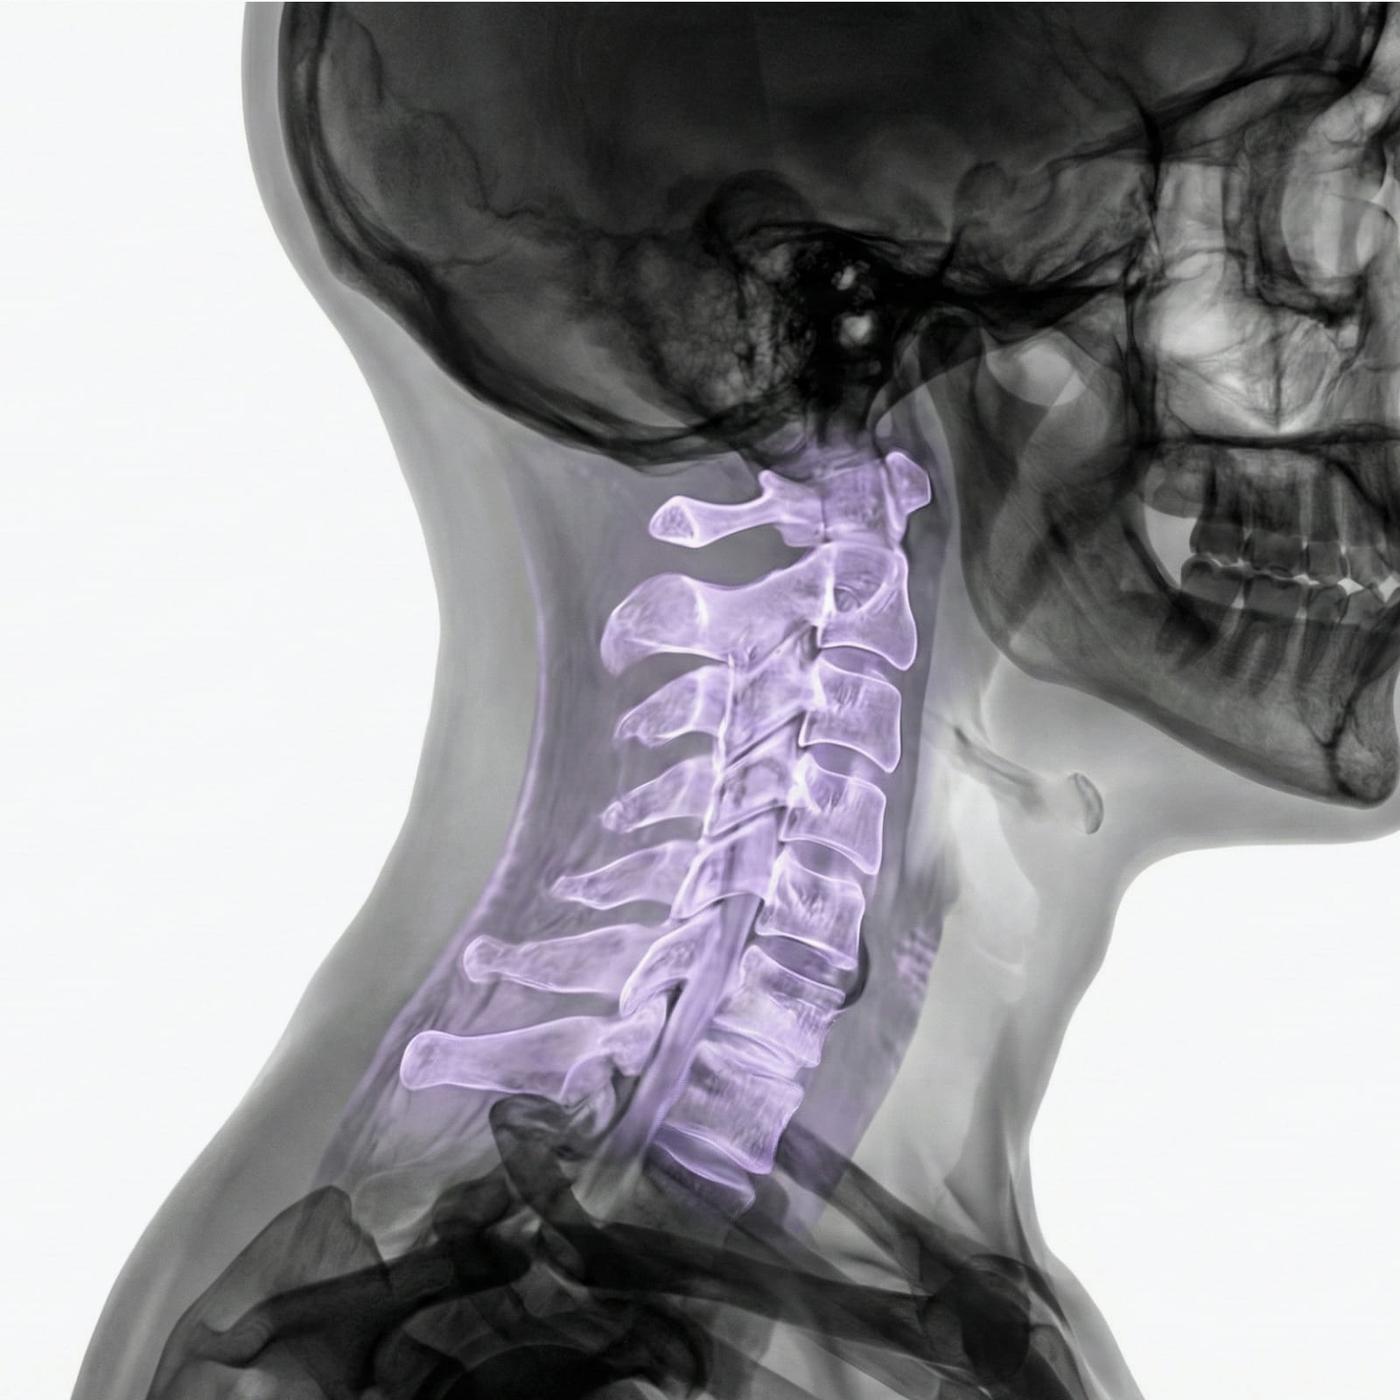

MR Halsrygg – Magnetröntgen vid nacksmärta, stelhet eller nervsymtom i armar och händer

Smärta i nacken som strålar ut i axlar, armar eller fingrar kan tyda på tryck mot nervrötter i halsryggen. Även stelhet, domningar, svaghet eller balansproblem kan ha sitt ursprung i förändringar i halskotpelaren. MR halsrygg är en skonsam och mycket detaljerad bilddiagnostisk metod som används för att kartlägga orsaker till dessa symtom – oavsett om de beror på diskbråck, artros, spinal stenos eller inflammation.

Undersökningen ger noggranna bilder av halskotor, diskar, ryggmärg, nervrötter och omgivande mjukdelar. Eftersom MR inte använder röntgenstrålning är den lämplig även för upprepade undersökningar eller för patienter där strålningsfrihet är extra viktigt.